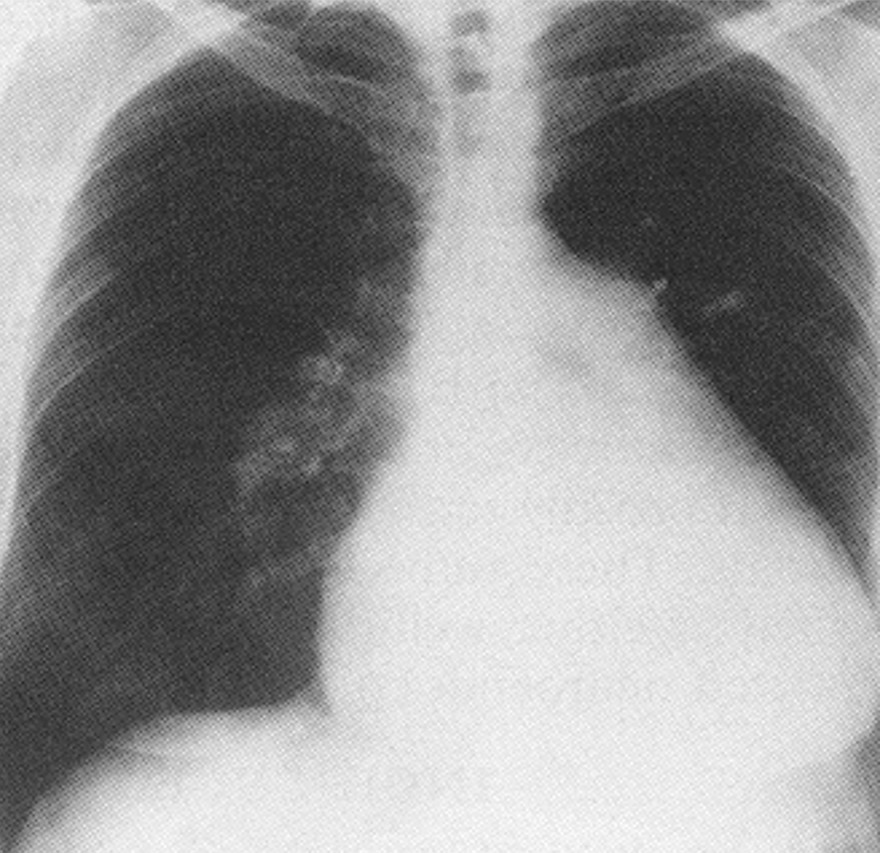

Admitting chest x-ray showing cardiomegaly and pronounced enlargement of the main

pulmonary artery segment - a sign of chronic pulmonary hypertension (left image).